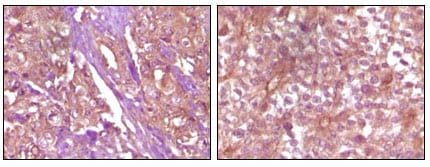

分类: 科研抗体货号: 20054别名: S100A6; 2A9; PRA; 5B10; CABP; CACY应用: IHC反应种属: Human

分类: 科研抗体货号: 20071别名: ECK; EPHA2应用: WB,IHC反应种属: Human